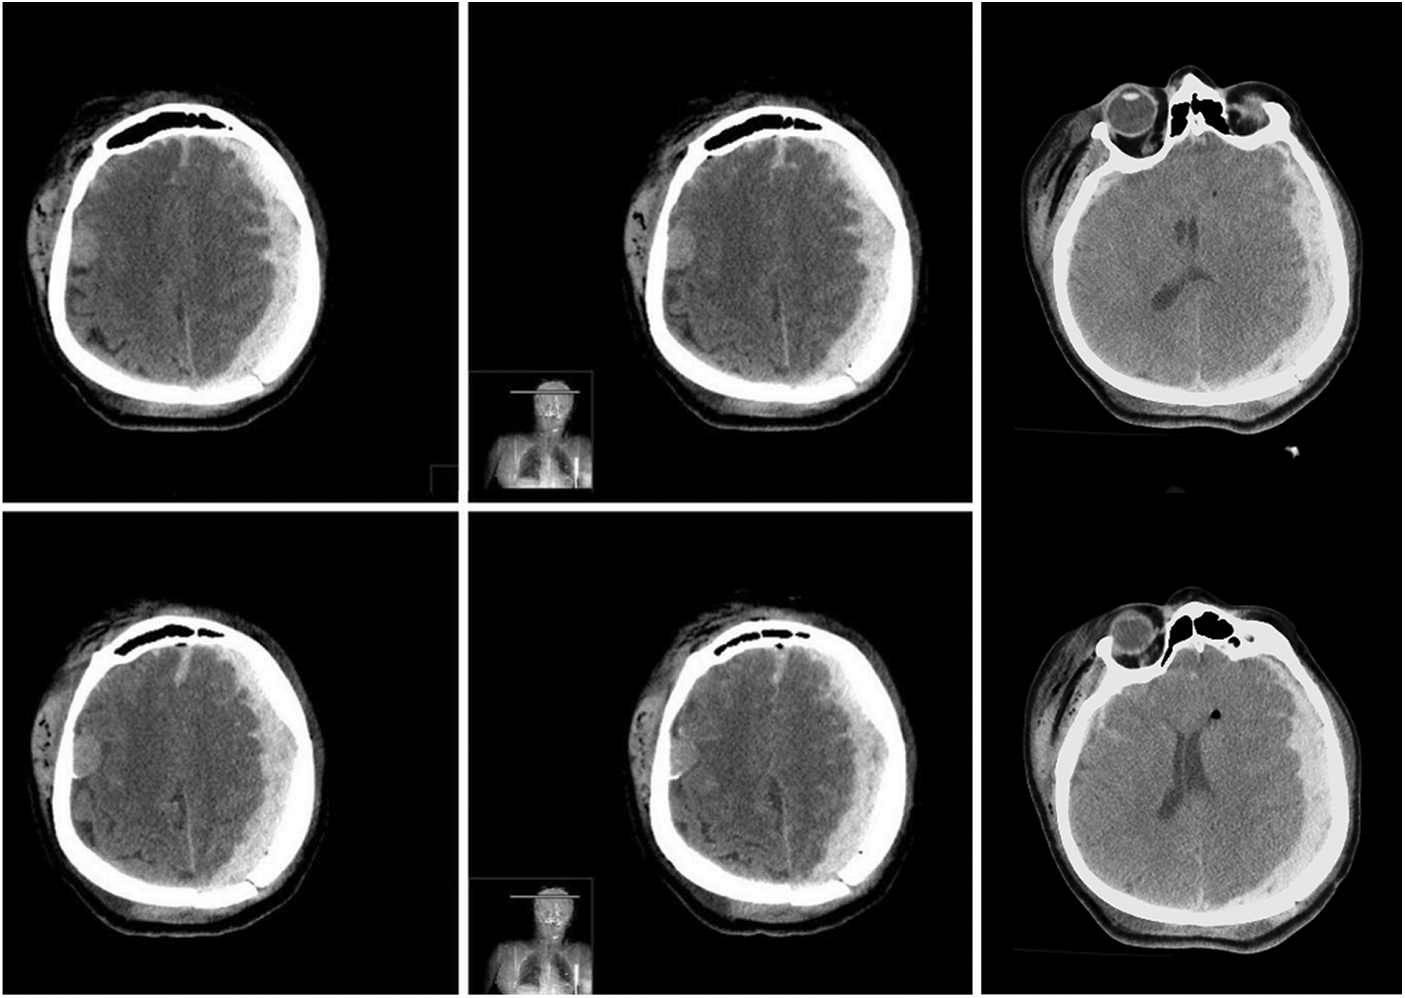

The patient was admitted to our emergency department with a Glasgow Coma Scale (GCS) score of 7/15 and isochoric, myotic pupils. An immediate head CT scan revealed a small acute SDH in the right hemisphere and an acute blood collection in the left hemisphere, which exerted mass effect on the brain, with contralateral midline shift (Fig. 2).

Figure 2: Pre-operative axial brain CT scan images in series showing a small right hemispheric acute subdural hematoma and a left hemispheric acute subdural hematoma (extradural blood component found intraoperatively), which exerted mass effect on the brain, with contralateral midline shift

Furthermore, we found a complex skull fracture across the superior sagittal sinus, the right frontal bone, and the left parieto-occipital bones with dislocation of fragments (Fig. 3).

Figure 3: Pre-operative brain CT scan with three-dimensional reconstruction showing a complex skull fracture across the superior sagittal sinus, the right frontal bone, and the left parieto-occipital bones with dislocation of fragments